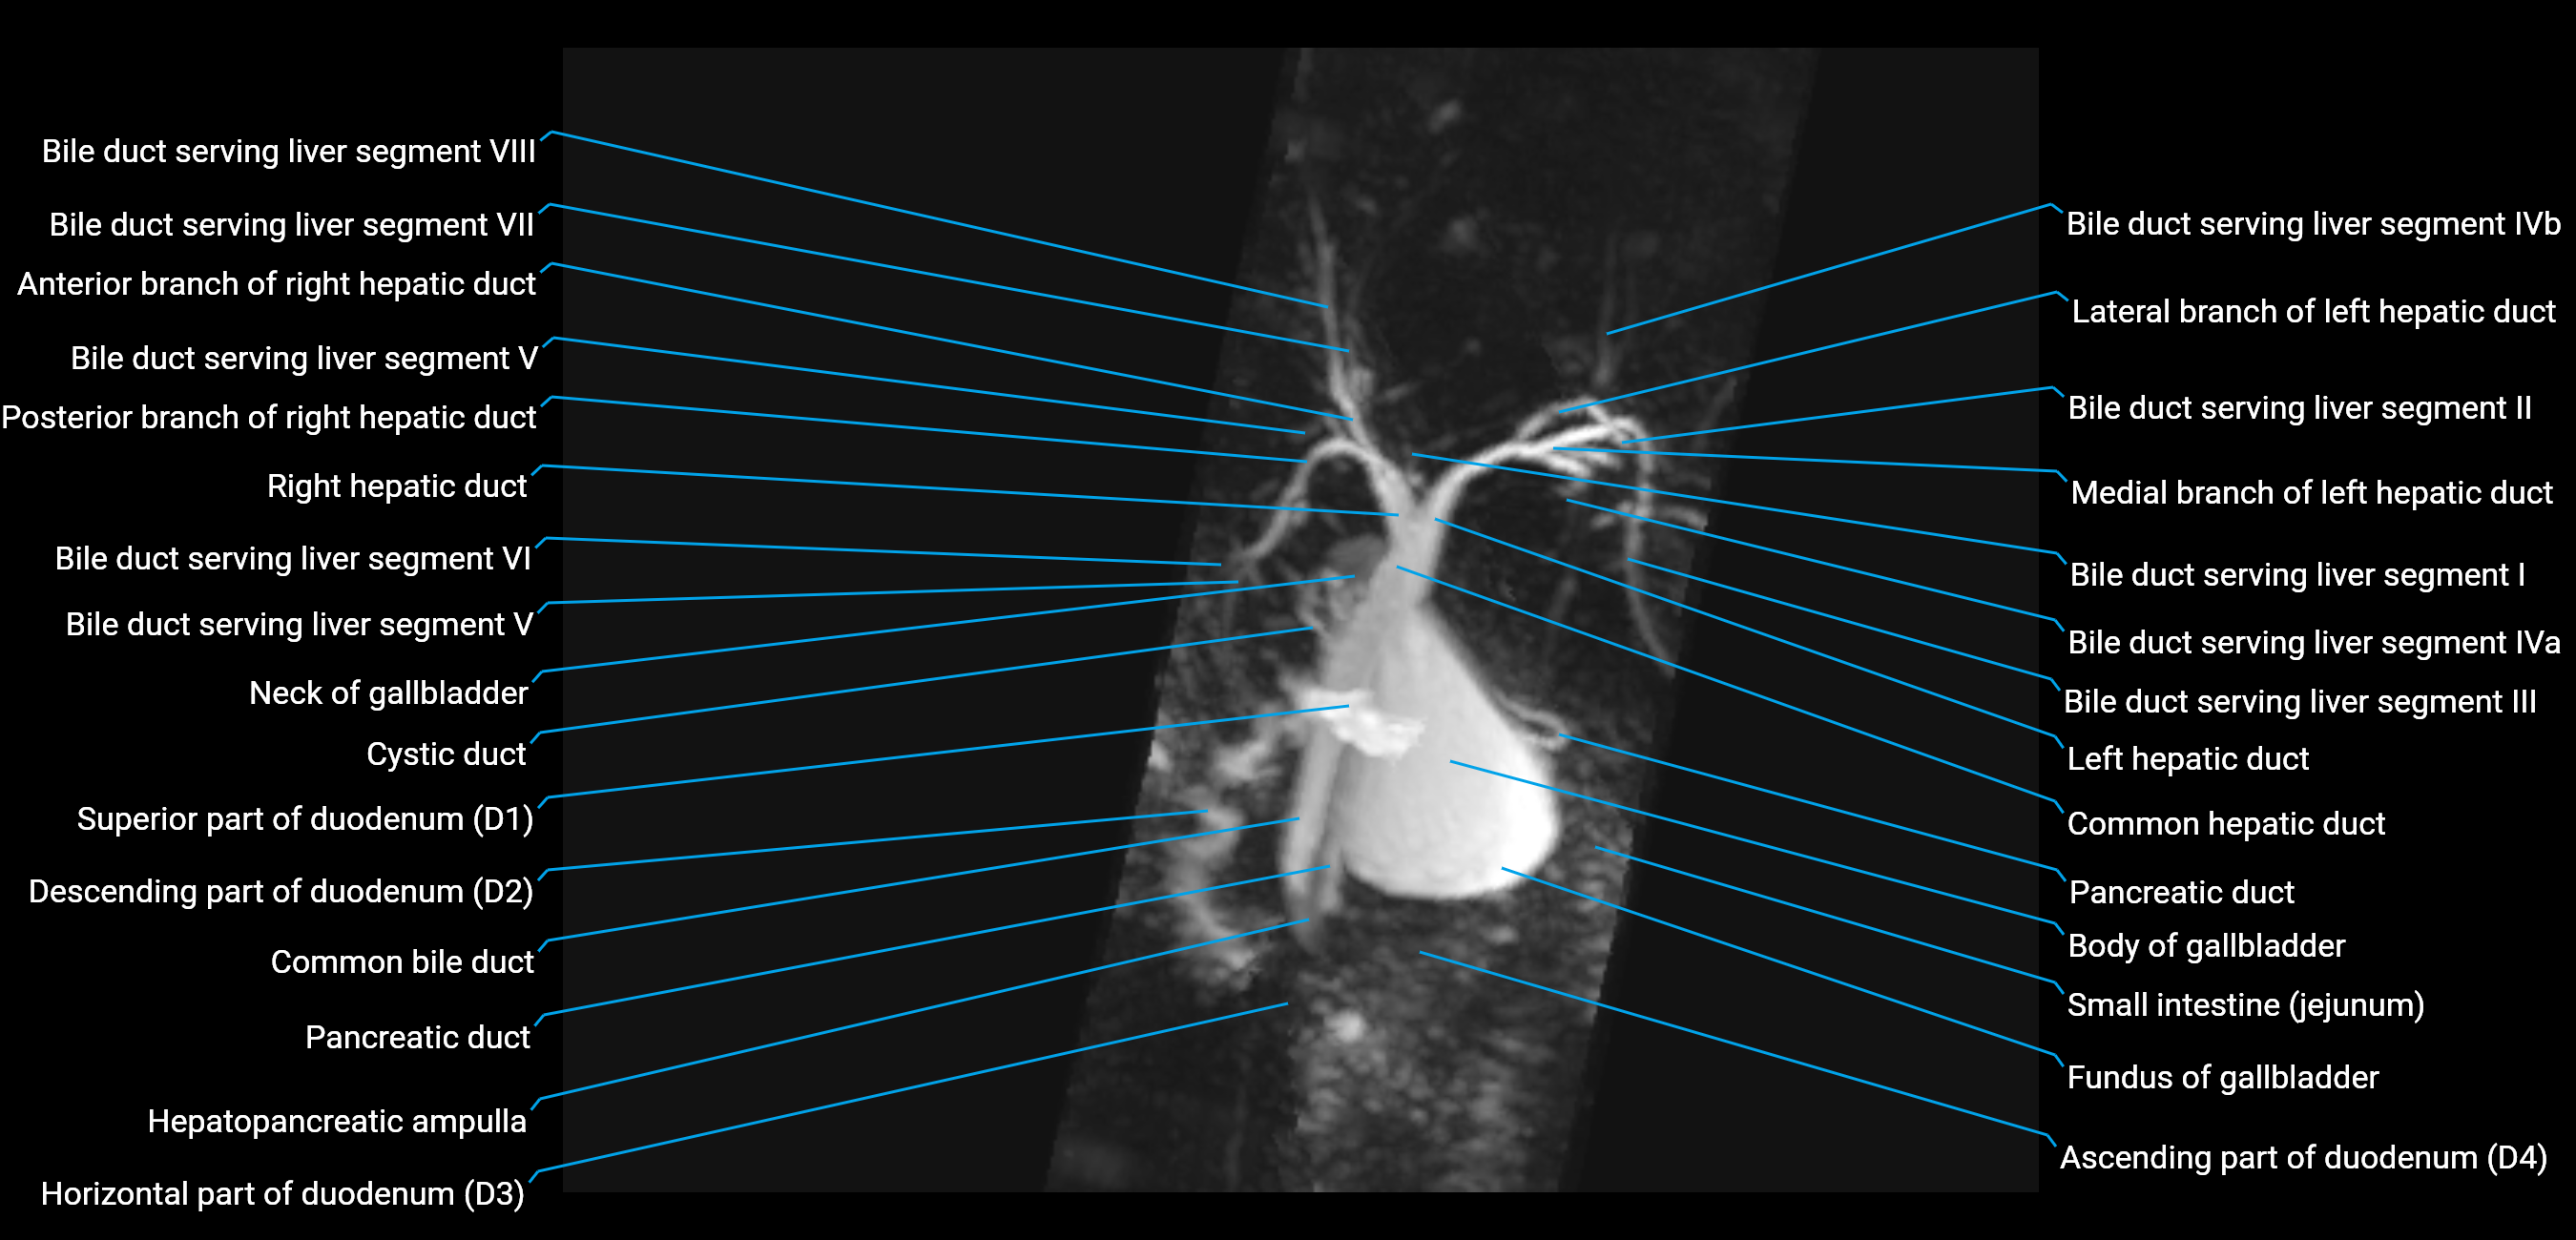

T2 TSE Fat-Saturated 3D (MRCP sequence):

• Duct visualized as a continuous bright tubular structure joining or parallel to the main pancreatic duct

• Allows 3D reconstruction of ductal anatomy and variants

• Excellent for diagnosis of pancreas divisum

Thick-slab T2 Fat-Saturated HASTE:

• Shows the accessory duct as part of the biliary–pancreatic system in a projectional image

• Highlights communication with main pancreatic duct and opening into the minor papilla

• Filling defects (stones, strictures) seen as dark spots within bright fluid

MRI image

image

Fullscreen Image